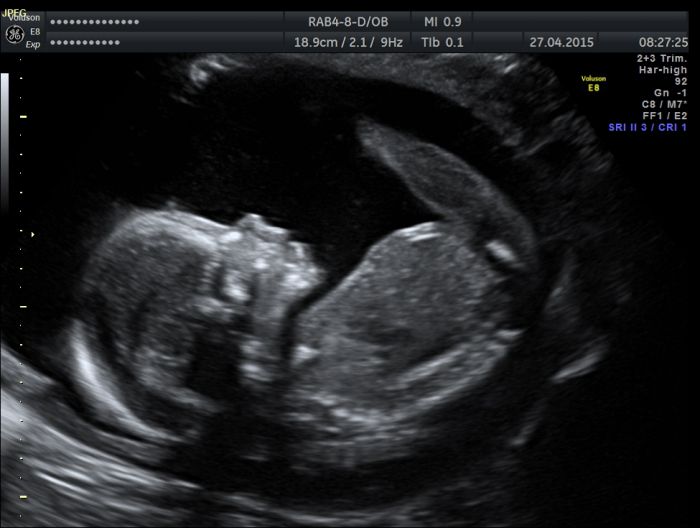

Dobré ránko všem ...tak jsem byla v pondělí na velkém ultrazvuku v Gennetu ...vše Ok ..a ukázali nám i toho pinďu, no fakt tam je

tak už tomu věřím ... bude to Kryštůfek.

Eviku ... krásná fotečka. A gratulace k dobrým zprávám.

[735077] Eviku, gratuluji k chlapečkovi. Krásná fotka, úplně mi připomněla moje první těhu. Mám úplně stejnou......s nataženými nožičkami.